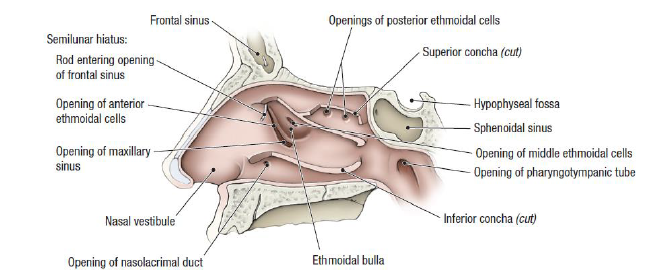

Paranasal sinuses

鼻旁竇,濕潤呼吸的空氣

Frontal sinus

神經皆CN V1

- Anterior ethmoid a.

- Supraorbital a./n.

- Supratrochlear (滑車上) a./n.

Maxillary sinus

來自Maxillary a. 3rd Part, Maxillary division

- Ant./mid. sup. alveolar a./n.

- Post. sup. alveolar a./n.

Ethmoid sinus

ethmoid bulla

Mid. ethmoid sinus 開口

Sphenoid sinus

Nose cavity

Nasal septum (鼻中膈)

- nasal sepal cartilage

- perpendicular plate of ethmoid

- vomer